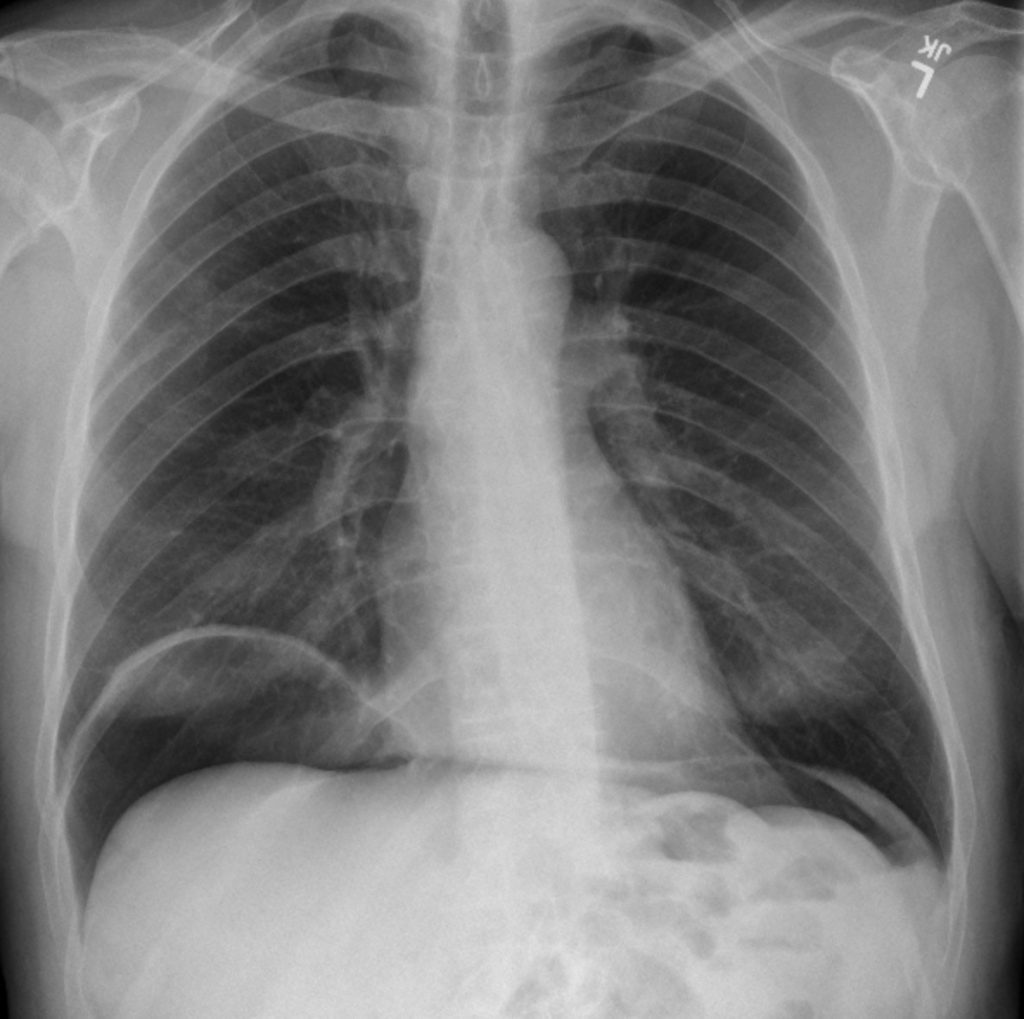

- Imaging: X-ray, ultrasound, CT scan (to detect free air or fluid).

| perforation peritonitis gas under diaphragm |